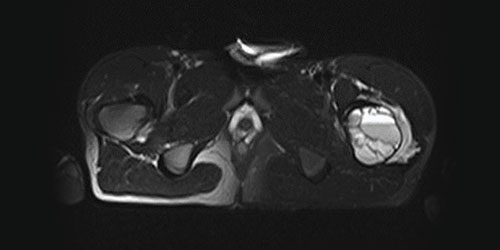

Спинальная метастаза представляет собой распространение рака на кости позвоночника, что часто вызывает боль в спине и другие симптомы. Ранняя диагностика и индивидуально подобранное лечение играют важную роль в улучшении качества жизни и эффективном контроле симптомов.